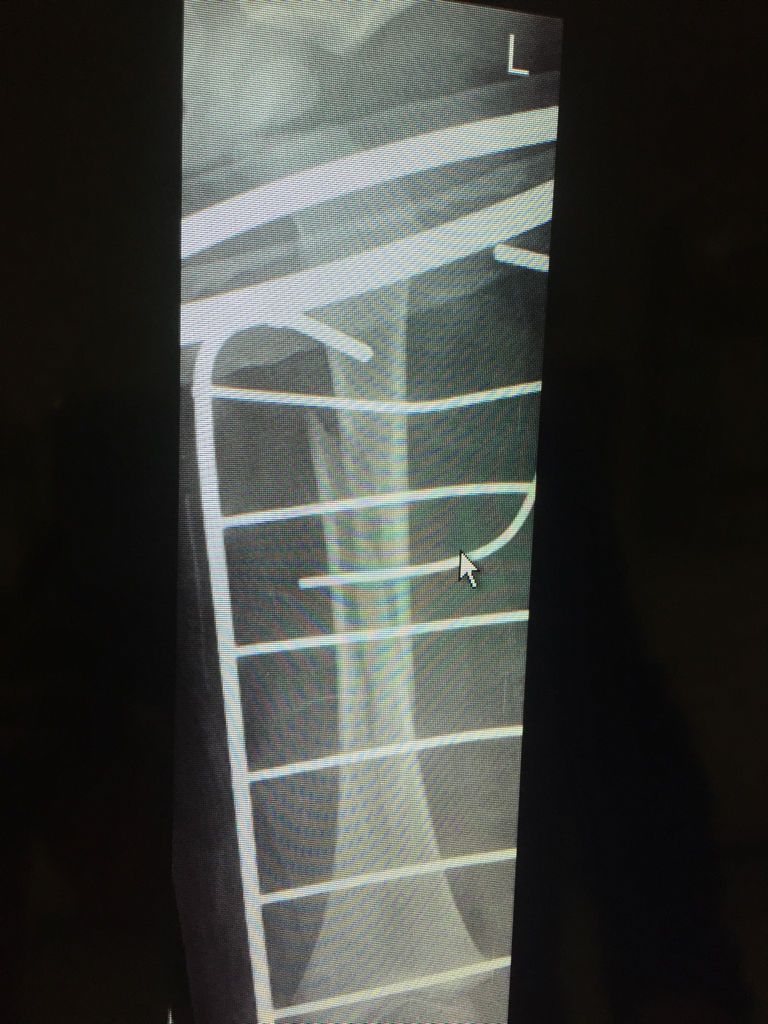

孩子2岁2个月,骨裂!骨科专家能不能帮我看看片子,能恢复好吗?现在医院 点击展开 匿名用户 2016-06-25 14:56 满意回答 这脂敢个骨折是长斜型骨折,可以恢复阶柴丰好,两岁小孩愈合能纪征力和纠正畸形能力强,一般没有问题,积极配合医生治疗就可以 ²¿L 2016-06-25 15:00 宝宝知道提示您:回答为网友贡献,仅供参考。 相关问题 急急急,麻烦小儿骨科大夫帮我看看片子,如何更能合适的治疗小孩? 宝宝一岁半了,昨天把大脚趾后的那根骨头砸骨裂了,现在打石膏了,医生说要一个月,请问平时需要注意什么 宝宝1岁2个月,最近要睡觉前老是会身子弓着,手指脚趾卷曲,去医院看了骨科和脑科都无异常,但孩子的表